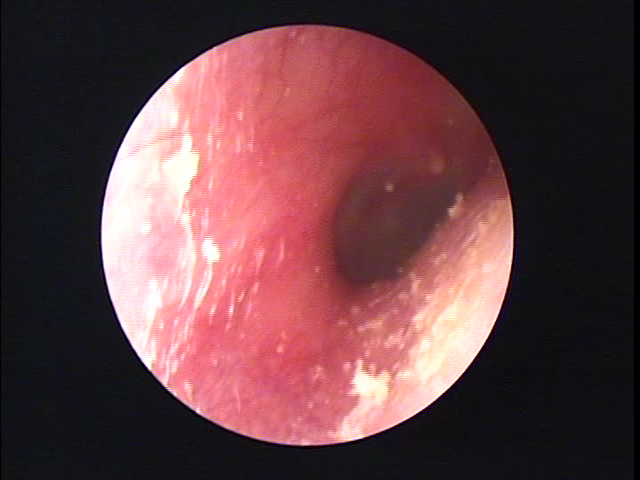

左耳の耳あか

左耳の耳垢そうじ 福岡市博多区

鼓膜のすぐ手前の下に黒い耳あかがあります。